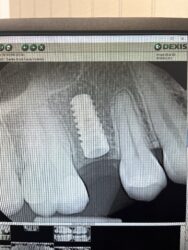

I have been placing Implant club implants for the past 2-3 years (yes Ivan, I know you that much), and my beautiful GF needed an implant. Extraction and bone grafting was performed. Today I did the uncover. 60% of my cases, I have notice this overgrowth of bone. This on was part of the statistics. I just wanted to show off/share the case.